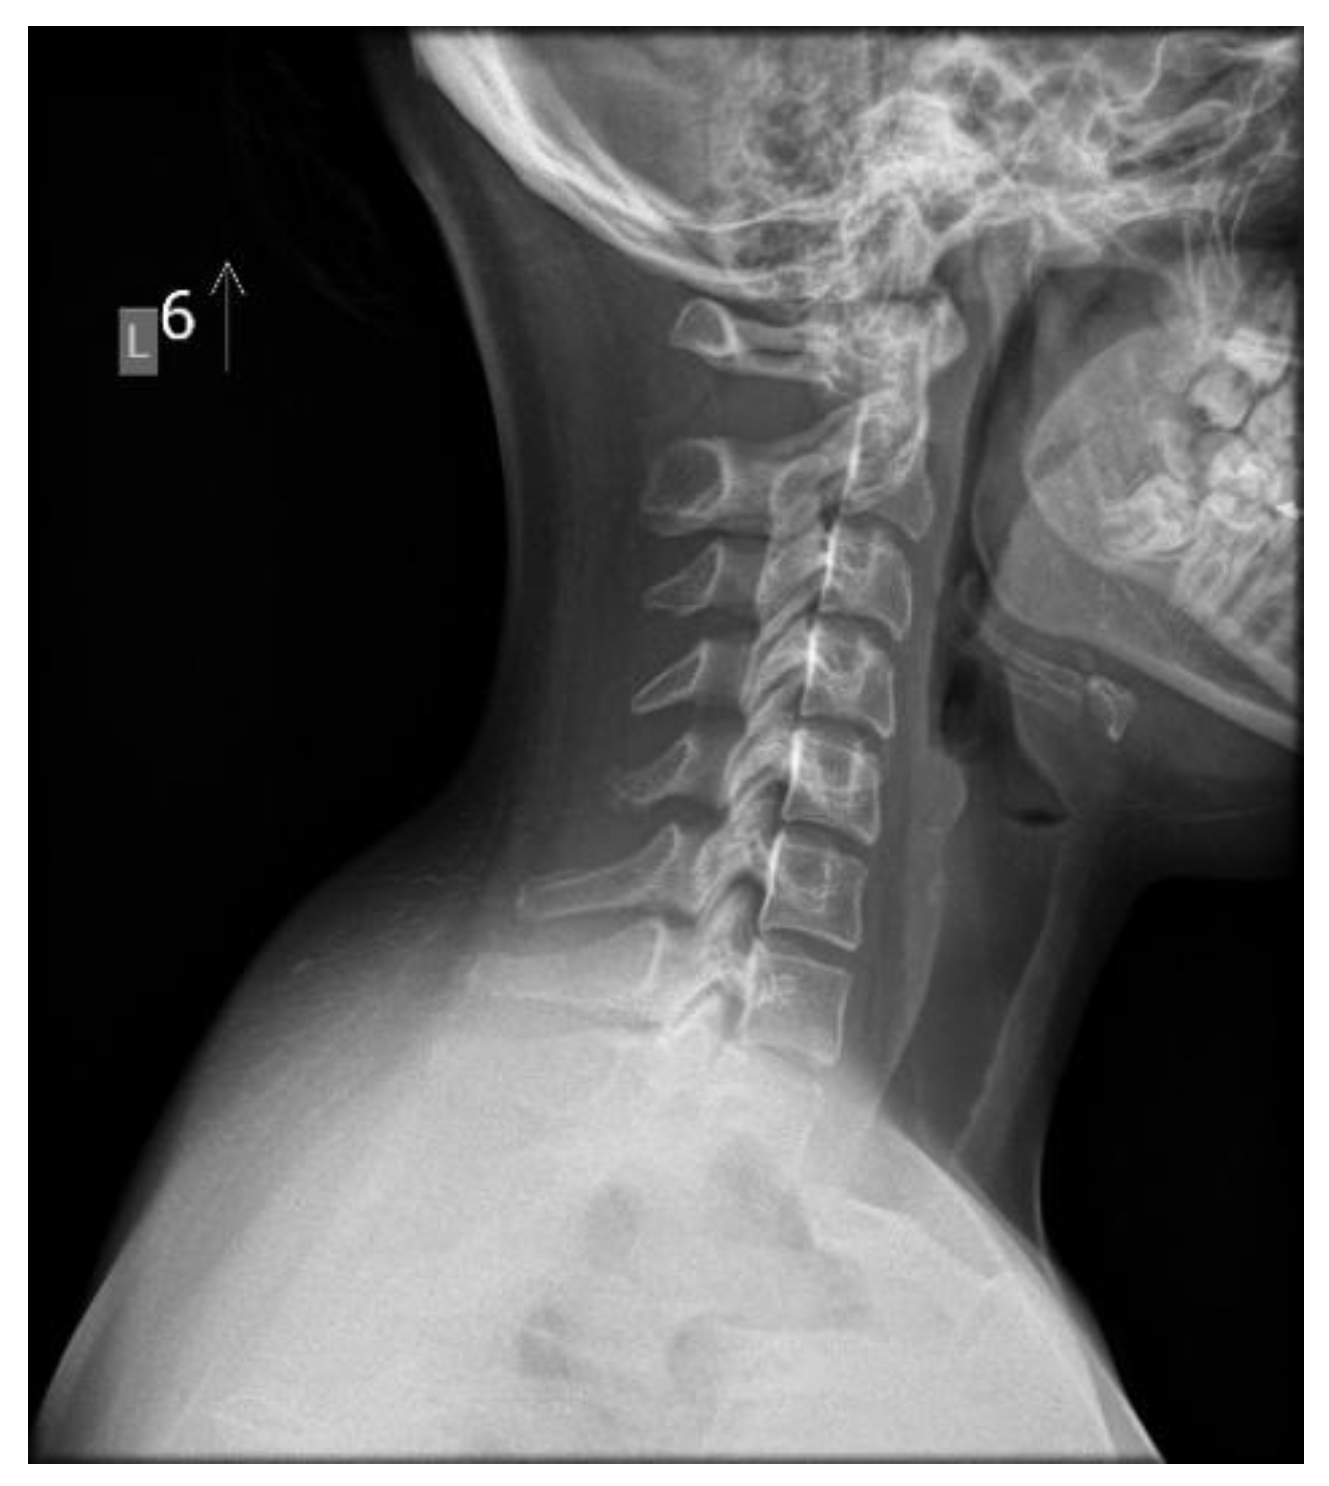

Anatomically, the spine exhibits four natural curvatures in the sagittal plane: cervical lordosis, thoracic kyphosis, lumbar lordosis, and sacral kyphosis. These natural curvatures are an evolutionary adaptation that enables the body to maintain an upright posture with minimal energy expenditure and maximum resistance to gravity [27,28]. Proper formation of these curvatures prevents excessive stress on intervertebral discs, ligaments, and muscles by efficiently distributing forces and transferring mechanical loads to each moving segment [29]. The biomechanical balance of the counter curves provides optimal stabilization of the entire spine. Disturbances to this mechanical system can contribute to a gradual and often prolonged process of tissue degeneration. Clinical symptoms appear when the compensation limit is reached and the critical point of permanent tissue damage is exceeded (Figure 2) [30]. The patients with abnormal physiological spinal curvatures and the absence of clinical symptoms, such as pain, do not necessarily indicate a normal state, despite the surprisingly high prevalence of such cases (Figure 3).

The cervical spine supports the weight of the head while enabling multi-directional movement. This is achieved through the deep muscles of the cervical spine, which aid in perception and stabilize posture, along with the vestibular system and visual input. The upper cervical spine, particularly C1–C3, and the occipitoparietal junction are particularly important. It is estimated that the suboccipital muscles contain a high number of spindles (proprioceptors) [55]. The activity of these mechanoreceptors can be affected by injury, inflammation, or degenerative changes [56]. Changes in loads and impulses in FHP result not only from overloads during work in a head-down position but also from persistent dysfunction. The cervical lordosis loss is a structural disorder that can be seen on neck X-rays in a relaxed, habitual posture (Figure 2 and Figure 3). Muscles have a high capacity to adapt to altered working conditions in non-physiological positions by shortening, atrophy, and degenerative changes. This can impair muscle strength and endurance, creating a vicious cycle whereby incorrect posture leads to changes in muscle morphology and innervation. These changes then cause weakened strength and neurocontrol, which further deteriorate stability and posture. These morphological changes in muscles also cause abnormal, continuous sensory impulses from the paraspinal and suboccipital muscles (deep stabilizers) to the central systems responsible for posture, balance, and coordination, resulting in information noise [56,57].

Figure 3. An asymptomatic 14-year-old girl with an inverted cervical spinal curve. Source: File from an outpatient.